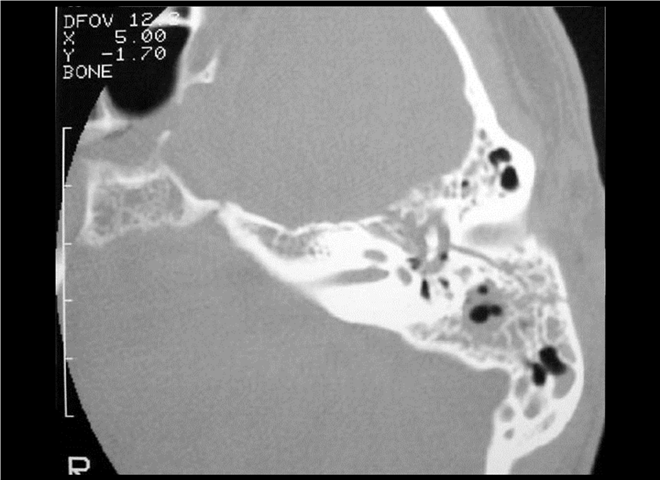

13_CT增强扫描